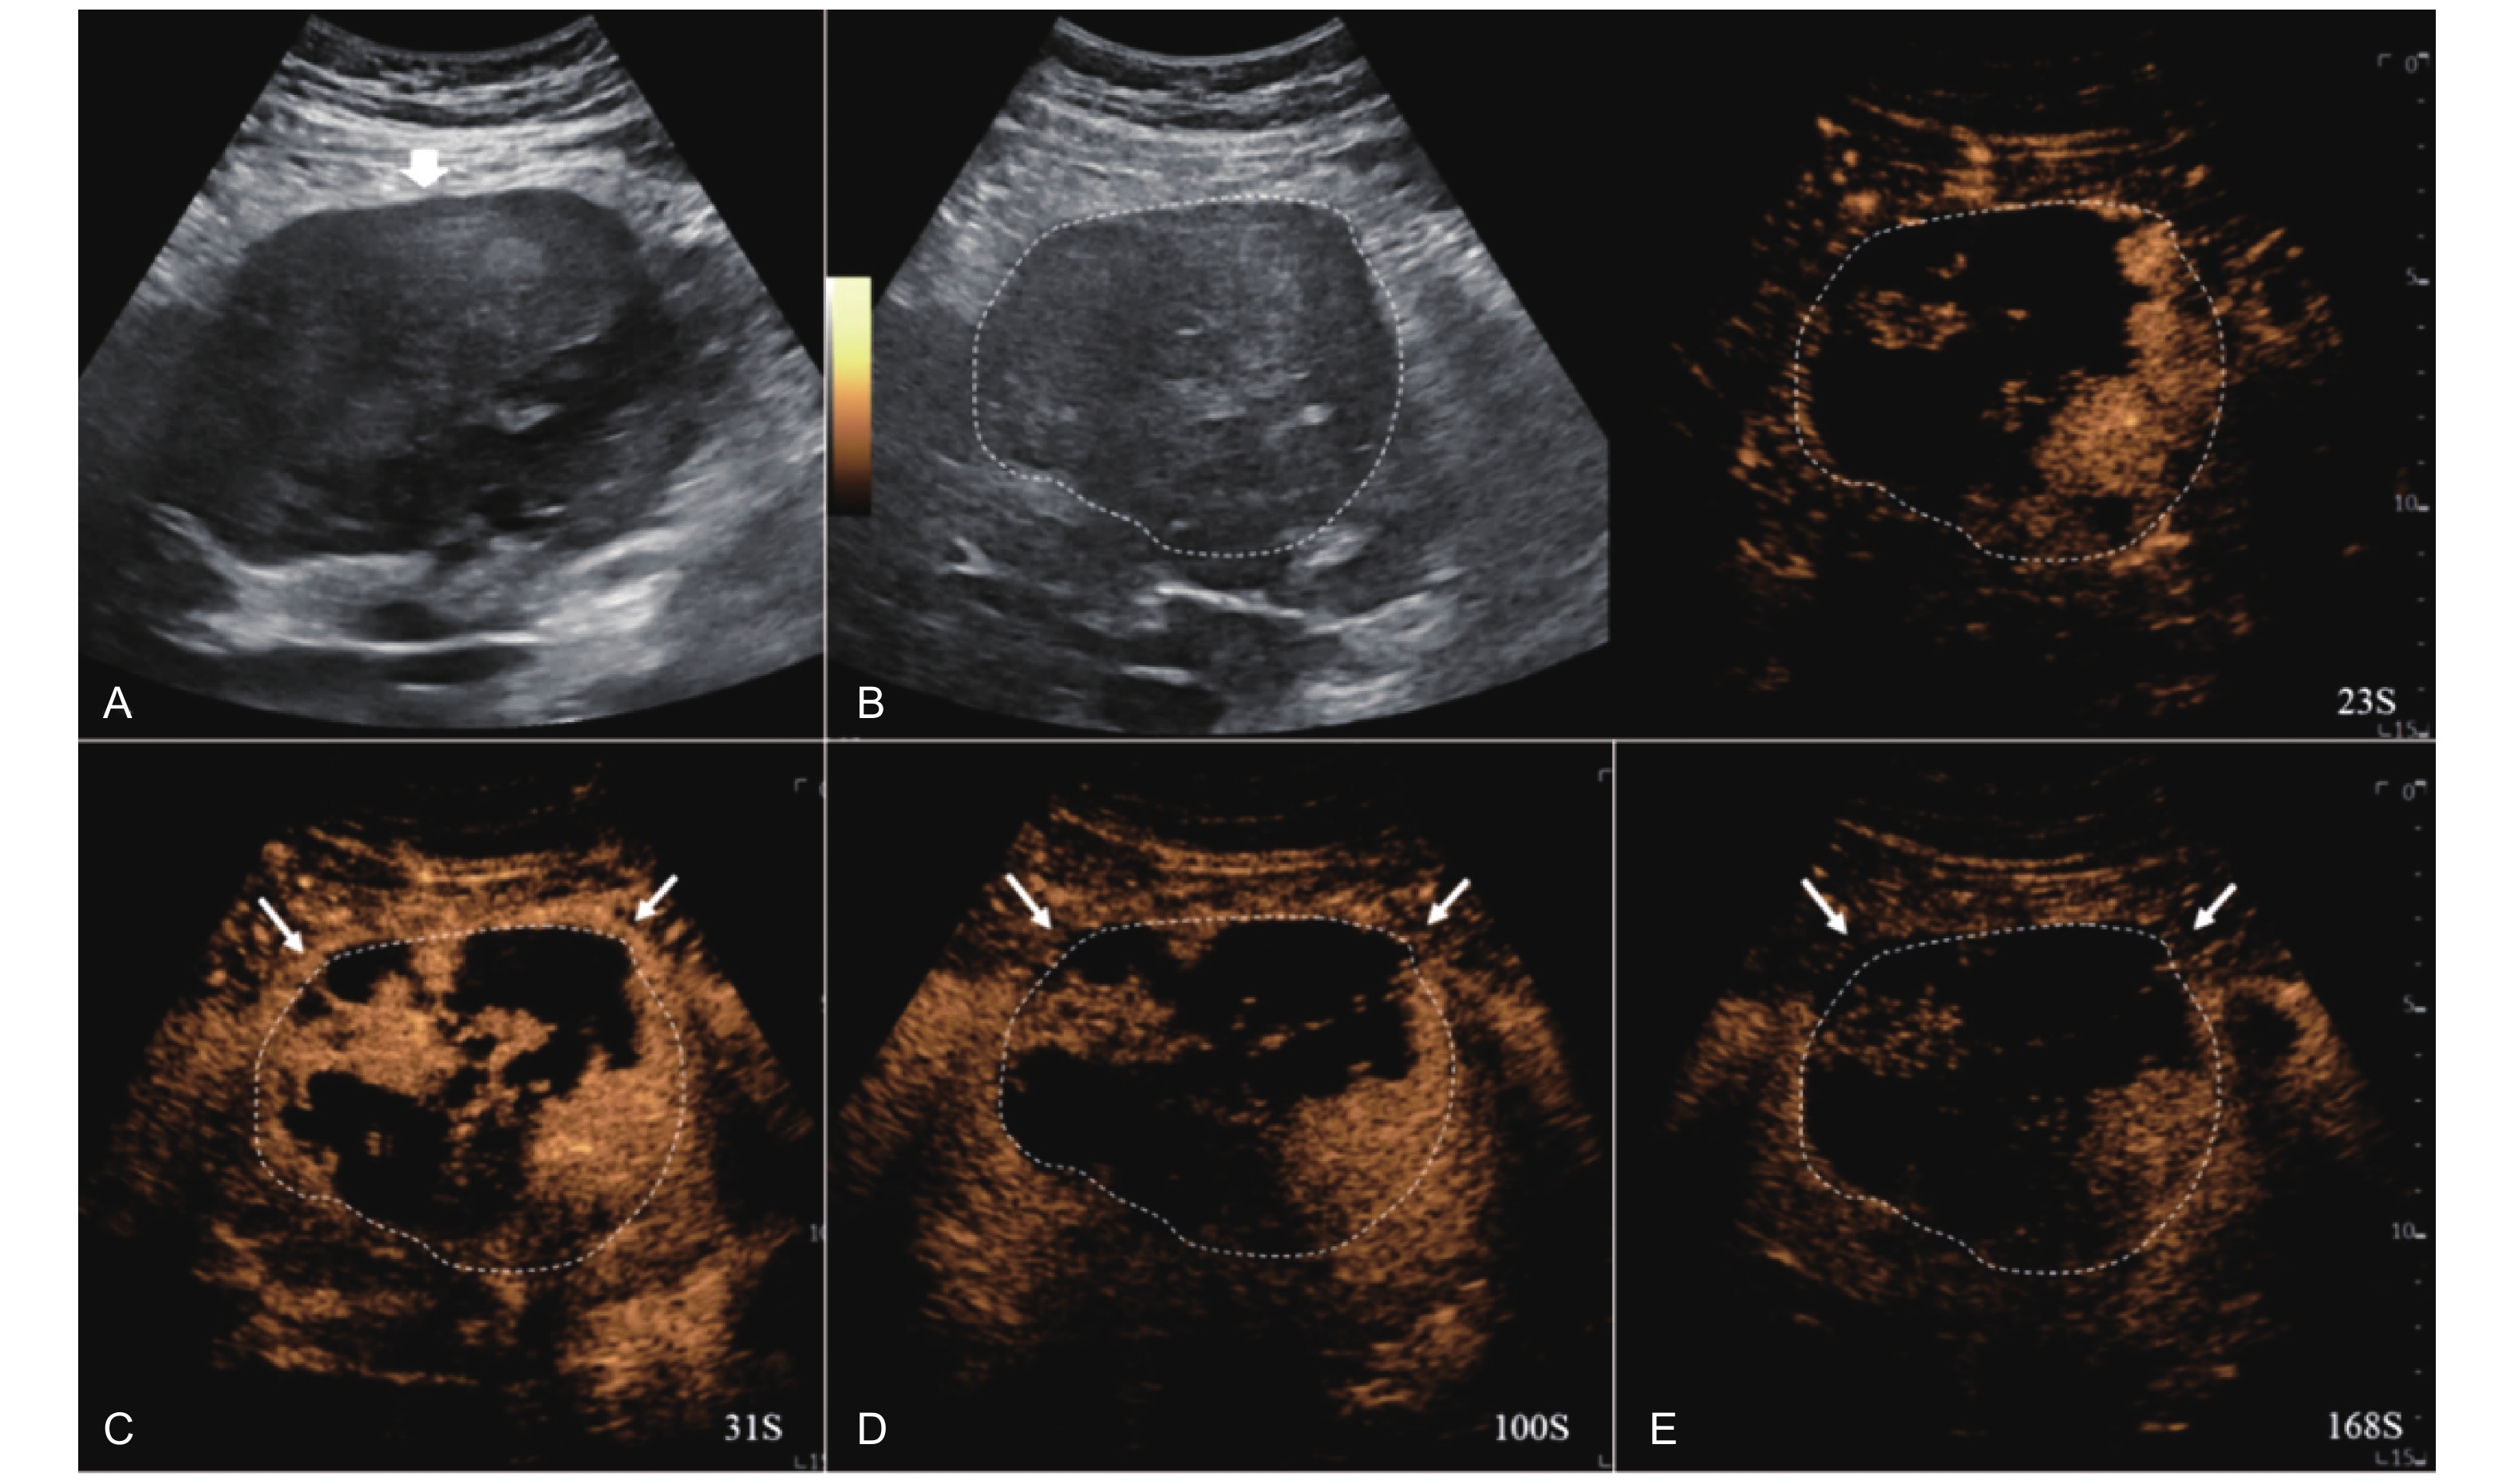

Figure 8

LR-TR Viable. Example of a treated tumor 36 days after TACE. (A) B-mode image shows a heterogeneous echogenic lesion (thick arrow) with irregular shape, measuring 115 mm in segment II and III; (B-C) CEUS shows intralesional heterogeneous hyperenhancement during the arterial phase; (D-E) The lesion shows partial mild washout in the portal venous and late phases. Perilesional enhancement remains identical to the surrounding liver parenchyma throughout all phases. Findings are consistent with LR-TR Viable."